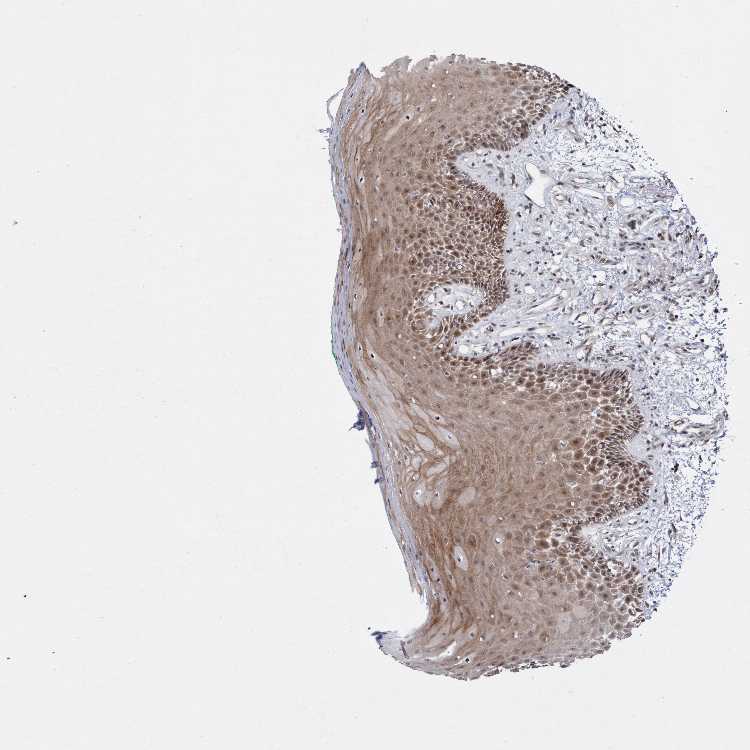

TISSUE PRIMARY DATA ORAL MUCOSA Show tissue menu

ORAL MUCOSA - Antibody stainingi

Antibody staining in the annotated cell types in the current human tissue is reported as not detected, low, medium, or high, based on conventional immunohistochemistry profiling in selected tissues. This score is based on the combination of the staining intensity and fraction of stained cells.

Each image is clickable and will lead to virtual microscopy that enables deeper exploration of all samples and also displays staining intensity scores, fraction scores and subcellular localization as well as patient and tissue information for each sample.

Antibody HPA022148Antibody HPA022896

Squamous epithelial cells MediumLow